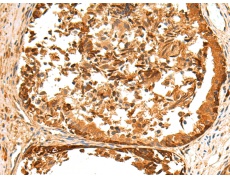

IHC positive control: |

Human tonsil and Human liver cancer; Human prostate cancer and Human gastric cancer |